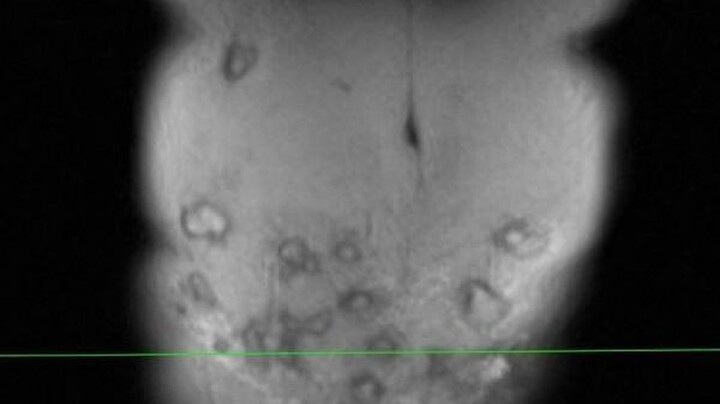

Cơ quan chức năng xác định, sản phụ T. tử vong do bị thuyên tắc mạch ối. Đây là một tai biến sản khoa do nước ối và tế bào thai nhi tràn vào mạch máu gây tắc mạch máu.